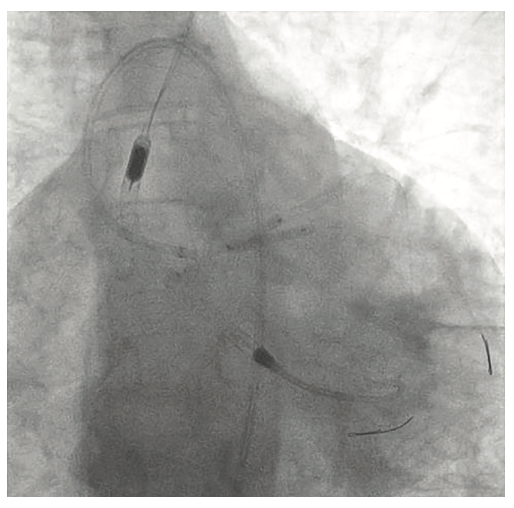

Following the Perclose placement, we upsized to a 14 Fr x 13 cm Cook Medical sheath (Figures 7-8), and through that, advanced a JR catheter into the ventricle and switched out for the Impella 2.5 device (Figure 9). A JR4 and eventually, an Amplatz right (AR) mod, was used from the right ulnar to engage the RCA, and an Extra Backup (EBU) 3.5, 7 Fr (Medtronic) was used from the groin. Dual angiography was performed (Figure 10). Once the activated clotting time (ACT) was >300 seconds, the ramus was wired with a Marvel wire (Boston Scientific). We attempted to cross the LAD CTO using a Corsair (Asahi Intecc) and a Pilot 200 (Abbott Vascular). The Pilot 200 crossed, but it appeared to be in the diagonal and could not be redirected down the LAD. A Gaia second (Asahi Intecc) was able to cross into the LAD (Figure 11), and at that point, was switched out via the Corsair for a workhorse wire, a Runthrough (Terumo). An 0.9 laser (Spectranetics) was used perform laser atherectomy for a minute and a half on the LAD (Figure 12), but we could not get the catheter across. However, this allowed us to advance a balloon across the lesion and we predilated with a 1.5 mm x 20 mm Mini Trek (Abbott Vascular) and then a 2.0 mm x 20 mm balloon. The same 2.0 mm x 20 mm balloon was used in the ramus. A 2.5 mm x 15 mm AngioSculpt (Philips) was used to predilate the LAD, but on its return, the AngioSculpt became stuck and would not come back. We got it partially into the guide and then the shaft broke. We had part of the catheter in the guide and part of it in the coronary (the left main). We initiated a series of procedures to remove the AngioSculpt, first attempting use of a GuideLiner (Vascular Solutions) to envelope the balloon, but this was unsuccessful (Figure 13). The GuideLiner kept pushing the device further out. We tried trapping it; that was also unsuccessful. We were able to get a Mini Trek balloon distal, thinking it could be inflated and pulled back; that did not work. We then put the 4 wires down, wrapped the wires around and pulled back, getting it partially in the guide, but we could not get it all the way in. We got a Mini Trek down, used the GuideLiner to put a 2.0 down, and attempted an anchor technique that did not work, but this time, when we pulled the Mini Trek 2.0 back, it dislodged the balloon. The AngioSculpt was able to come in the guide and was removed without losing wire position. We rewired the ramus, performed dilation of the LAD and ramus with a 2.5 mm noncompliant balloon, and performed intravascular ultrasound (IVUS). The LAD was about 2.75 mm2 distally and the ramus was 3.0 mm2, with the left main being approximately 3.75 mm2. A double kissing (DK) crush technique was used with a 2.75 mm x 38 mm Synergy stent (Boston Scientific) to the LAD and 3.0 mm x 24 mm Synergy to the ramus; then we used proximal optimization technique (POT) with a 3.75 mm NC balloon (Medtronic) and a final kiss with 3.0 mm x 20 mm NC balloons (Figures 14-17). IVUS was used to confirm that the stents were well apposed. The Impella device was weaned and removed, keeping the sheath in. From the groin sheath, a balloon was advanced into the left subclavian and we did a dry close. We inflated an 8.0 mm x 40 mm balloon at 3 atmospheres (nominal is 6 atmospheres) (Figure 18). Once the pressure tracing from the axillary sheath side arm dropped, we were able to remove the sheath and then completed the Perclose. There was some slight track ooze (Figure 19). Therefore, we performed two 5-minute inflations with the 8.0 mm x 40 mm balloon at 3 atmospheres (nominal is 6 atmospheres), and there was complete resolution of the track ooze. No extravasation was noted (Figures 20-21). The ulnar sheath was sutured in, we made sure there were no issues overnight, and the patient was discharged the following morning.